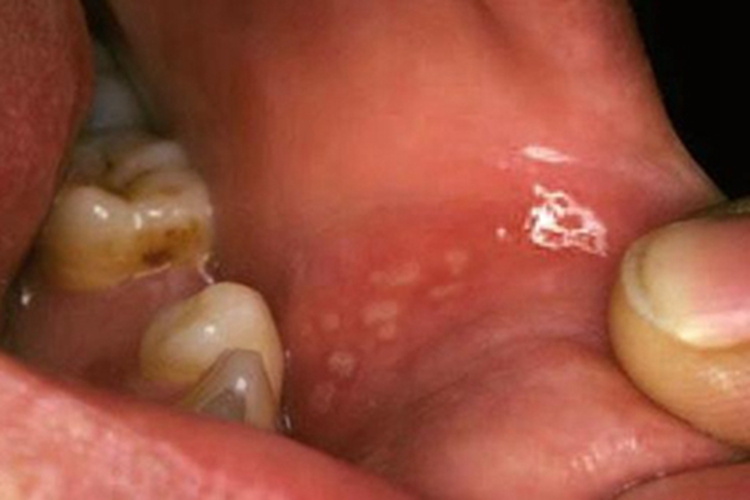

创伤性溃疡可在口腔黏膜出现水疱,之后破损后可形成溃疡或糜烂面,开始时可能仅有轻微疼痛或肿胀,溃疡为形态不整,有角的黏膜缺损,因唾液的浸渍,可使溃疡底发白,周边轻度炎性潮红,自觉疼痛。此外,表面渗出液和唾液混在一起,发生溃疡后可影响进食。

创伤性溃疡主要与口内持久的机械刺激有关,如残冠、残根、不良修复体、锐利的牙齿边缘等。